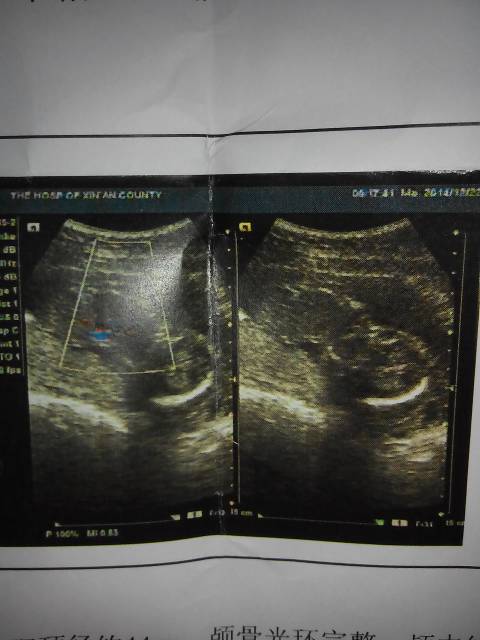

麻烦懂得帮我看看,这胎儿有手脚么 麻烦懂得帮我看看,这胎儿有手脚么 点击展开 玮晨妈妈 2014-12-25 08:47 为您推荐: 其他回答 有啦的!。 荥洋嘛嘛 2014-12-25 19:57 听医生的没错 小儿美👜👛🎒童品 2014-12-25 16:52 嗯你就放心吧 平平淡淡_0uUH 2014-12-25 11:32 看出清楚,你让医生帮你看看 平平淡淡_0uUH 2014-12-25 11:27 看不懂,,, 花开、那瞬间 2014-12-25 11:22 加载更多 相关问题 做四维彩超30周4天宝宝手脚偏短3周,麻烦你帮我看看正常吗?非常感谢!